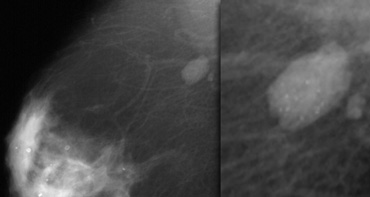

Notice the distortion of the normal breast architecture on oblique view (yellow circle) and magnification view.

A resection was performed and only scar tissue was found in the specimen.